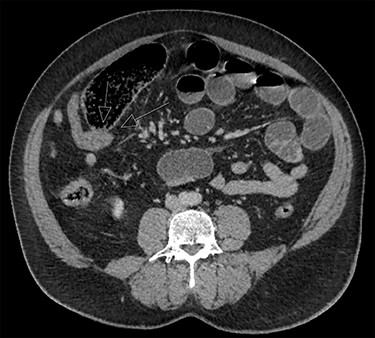

CT abdomen findings from Cases 1 and 2 showing distal SBO with the transition point in the pelvis. (a) Case 1 CT axial view. (b) Case 1 CT coronal view.

Case 1 is a 24-year-old male with a virgin abdomen who presented with a 3-day history of crampy abdominal pain and vomiting. He was haemodynamically normal and afebrile. He had tenderness in the lower abdomen and no peritonism. There was a moderate leukocytosis with a WCC of 12.7 × 109/L. An abdominal CT demonstrated distal SBO and a transition point located in the right pelvis and a small amount of free fluid (Fig. 1). The appendix was identified as normal. On Day 0 of his admission, he underwent a diagnostic laparoscopy. Intra-operatively, an MD was found at the site of the transition point between small bowel dilated proximally and collapsed distally (Fig. 2). Enteric contents were thickened raising the possibility of a faecolith. Macroscopically, the MD appeared to be normal, with no features of intussusception, volvulus or inflammation at the site. The MD was exteriorized through a mini-laparotomy and small bowel resection with a side-to-side stapled anastomosis was performed. Histopathology revealed MD with no features of inflammation or ectopic mucosa.